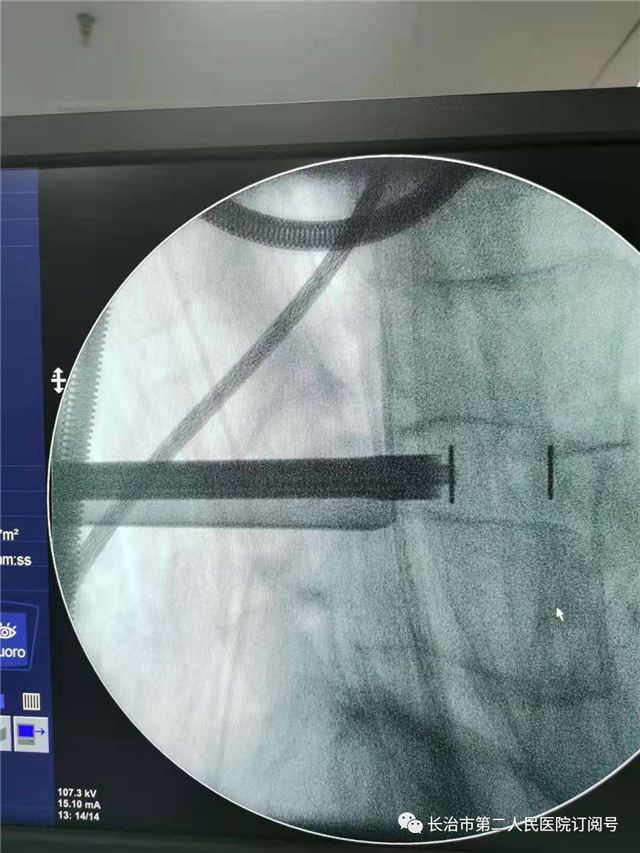

植入融合器

相较于以往采用的椎间孔镜治疗方法,大通道脊柱内镜提供了更广阔的操作视野和更全面的镜下操作工具,可实现脊柱内镜下的减压、融合、固定,在达到开放手术治疗效果的同时,还具备手术创伤更小、术中出血更少,术后恢复更快等诸多优点。尤其是适合年龄偏大,并发症较多,不能耐受传统开放手术问题的高龄患者。该脊柱内镜微创手术也是我院新开展的技术之一,具有较强的临床实际意义。

术后影像科室推荐